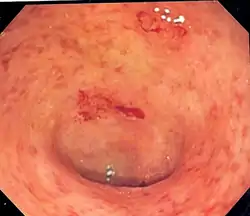

![]() صورة بالتنظير الداخلي لمقطع من الأمعاء معروف باسم القولون السيني (على شكل الحرف الإنجليزي S) مصابة بالتهاب القولون التقرحي، والسطح الداخلي للقولون فيه بقع وجروح في بعض المناطق. صورة بالتنظير الداخلي لمقطع من الأمعاء معروف باسم القولون السيني (على شكل الحرف الإنجليزي S) مصابة بالتهاب القولون التقرحي، والسطح الداخلي للقولون فيه بقع وجروح في بعض المناطق. | |